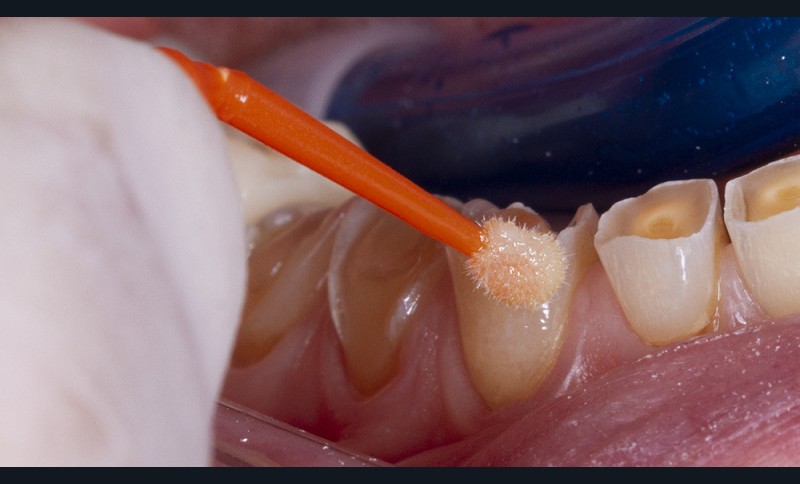

L’option utilisant des composites nano-hybrides nécessite, au préalable, de les déposer en quantité suffisante dans la clé transparente (fig. 6). Celle-ci est ensuite repositionnée sur les dents et les composites sont photopolymérisés à travers la clé.

Une résine de faible viscosité (flow), mais très chargée, peut faire office d’alternative à ces composites hybrides (par exemple, Grandioso Heavy Flow (Voco) ou Gaenial Universal Injectable (GC)). En effet, ces résines très fluides contiennent entre 78% et 83% de charges en poids [21], équivalent de ce fait aux composites hybrides précédemment cités. En effet, a contrario des autres résines dites flow (qui ne contiennent qu’environ 60% de charges [22]), ces dernières assurent une résistance et une dureté efficace, dans le temps requis. De plus, leur mise en pratique est simplifiée et nécessite moins de matériel.

Le remplissage du moule au composite doit se faire a minima ; il est en effet plus simple de compléter les quelques manques de matériaux en bénéficiant de la pellicule d’inhibition à l’oxygène que de retirer des excès conséquents. Il est aussi recommandé de procéder à une double enduction en injectant directement le composite flow dans les cavités érosives en parallèle du remplissage de la clé. Les excès relatifs de composites seront éliminés après polymérisation complète à l’aide d’une lame froide de bistouri ou d’une fraise adaptée de faible granulométrie.